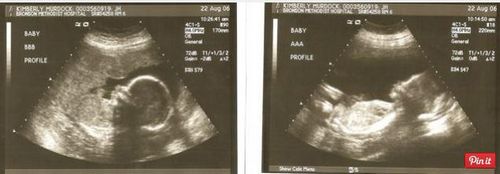

Фото: двійня на узі 23 тиждень.